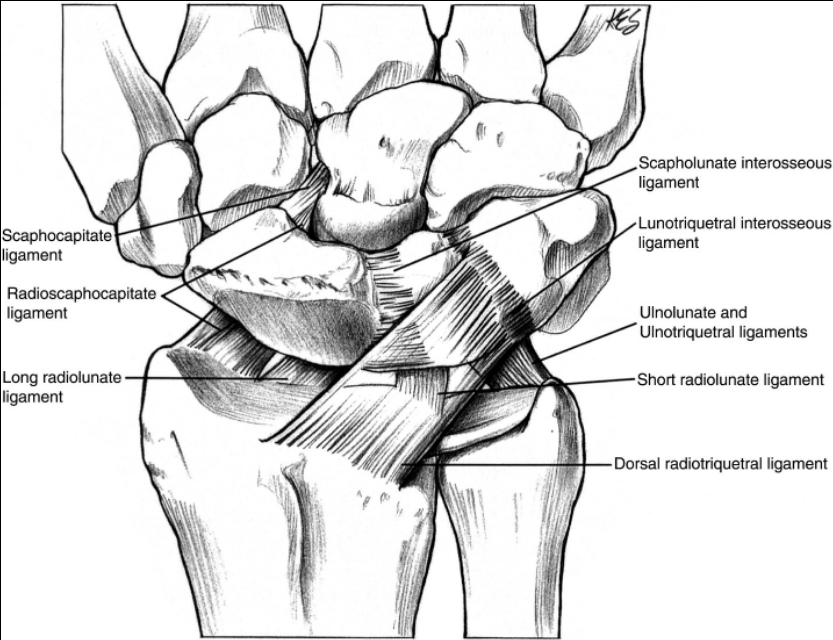

舟骨骨折是急诊中常见的损伤,占所有手部骨折的11%,占腕关节骨折的60%;舟骨表面80%被软骨覆盖,70%-80%的动脉供应由桡动脉分支提供,以逆行的方式进入背嵴。

最后,近极骨折可能有最大的风险不愈合或缺血性坏死。对这一事实的解释是,供应近极的动脉在这种骨折中受到损伤,70%的循环是逆行的。因此,近极骨折的骨不连发生率达到90%。

舟骨近端三分之一骨折的经皮固定技术

然后通过皮肤上的一个小切口,向舟状骨顶点(仅被背侧关节囊和皮下组织覆盖,通常在其路径上没有肌腱或神经)方向, 沿舟状骨月骨韧带桡侧1-2 mm将一根1 mm的导丝引入。 12或14号针可用于帮助通过导线(图3B-E)。如果没有达到合适的位置,可以使用较粗的导线(例如1.5 mm)。引入空心钻头(图3F),并使用比测量长度短4-5mm的螺钉,因为生物力学研究表明,螺钉越小,固定效果越好。用图像增强器评估最终螺钉位置和骨折压缩(图3G-I)。术后仅使用敷料和弹性绷带(图3J)。